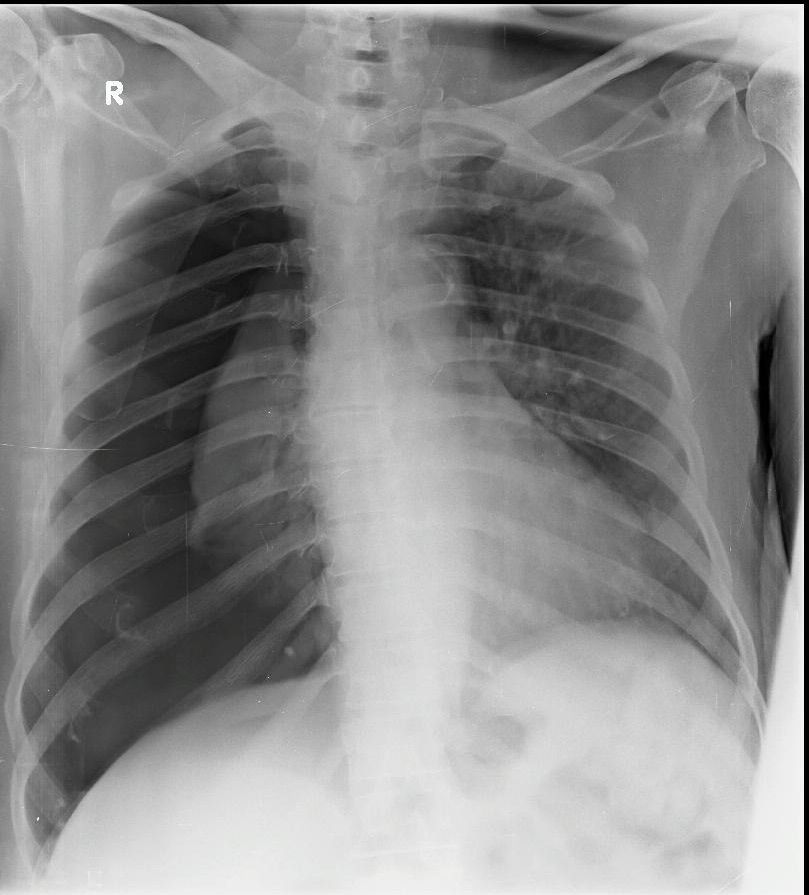

55yrs old male patient admitted for debridement for ah diabetic foot on pre operative work up found to be having spontaneous right pneumothorax thorax with out fall in saturation at room air. Right ICD insertion done and taken up for debridement